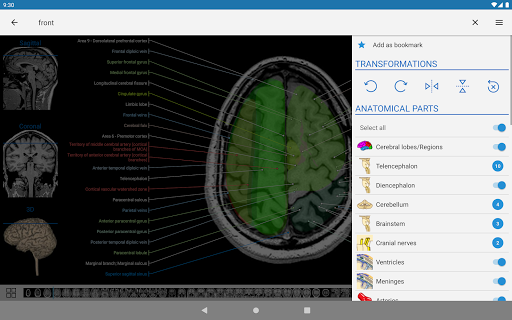

- يمكنك الآن استخدام قائمة الإعدادات والتمرير عبر الصور في نفس الوقت على الأجهزة اللوحية

- يمكنك الآن إخفاء الهياكل واحداً تلو الآخر (زر جديد داخل نافذة الوصف المنبثقة) وعرضها مرة أخرى في القائمة الصحيحة